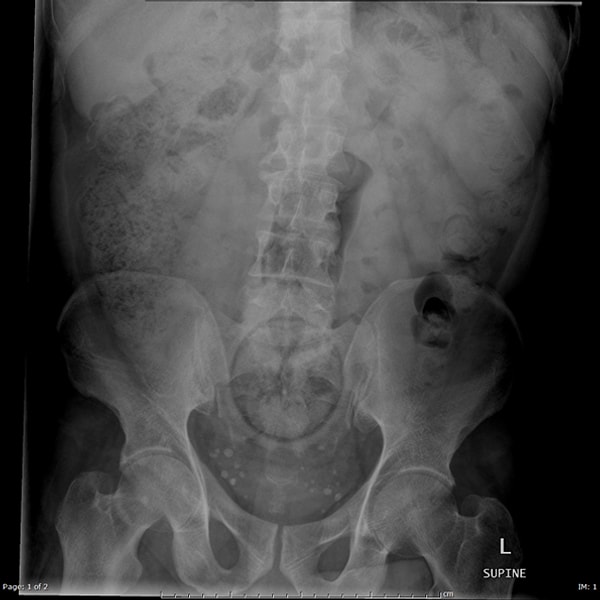

Итак, вашему вниманию предоставляются сами снимки. Попробуйте угадать, что там за предмет, если не сможете, то внизу есть подпись.

Яйцо.